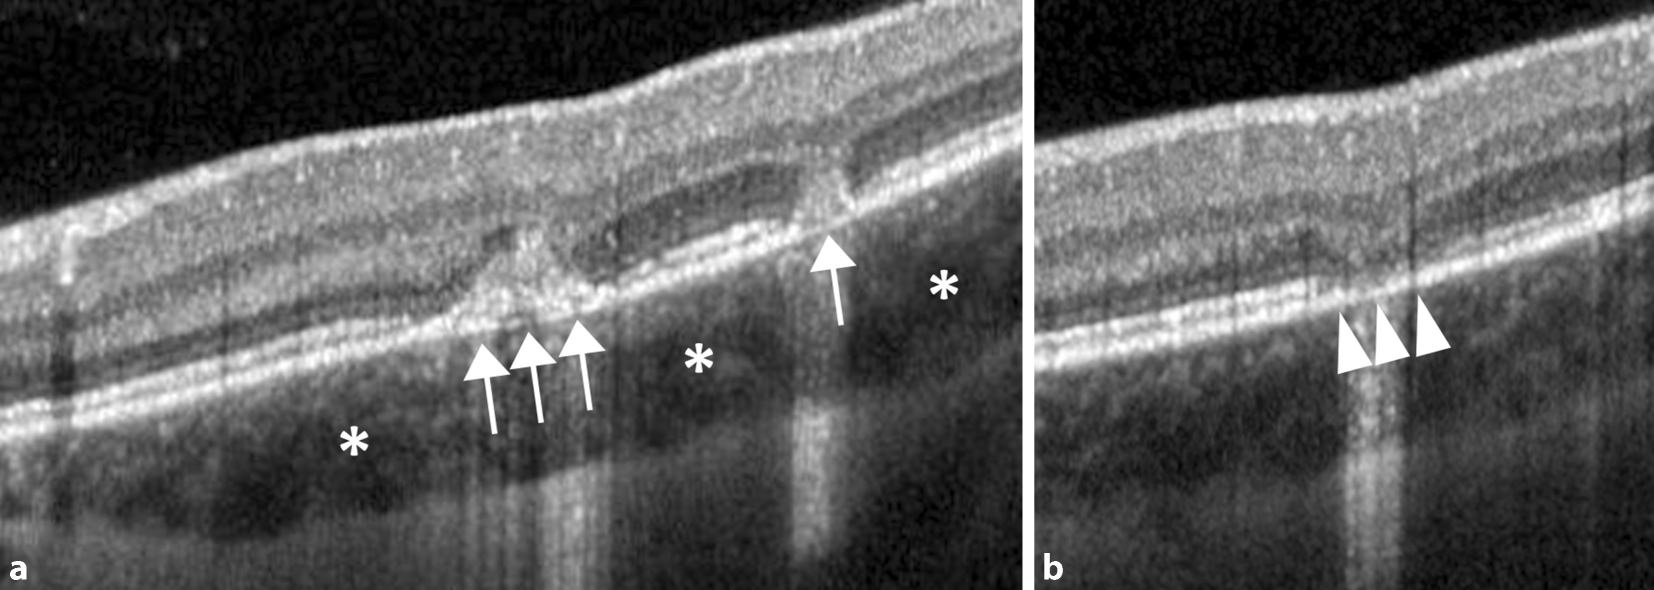

Abb. 2

Optische Kohärenztomographie der Makula des linken Auges bei Erstvorstellung durch unterschiedliche chorioretinale Herde. Es zeigen sich sowohl hyperreflektive Veränderungen im Bereich der äußeren Körnerschicht und äußeren Grenzmembran (Pfeile) als auch fokale Atrophien der äußeren Netzhautbanden (Pfeilspitzen). Zusätzlich wirkt die Choroidea verdickt (Sterne)

Bild vergrößern